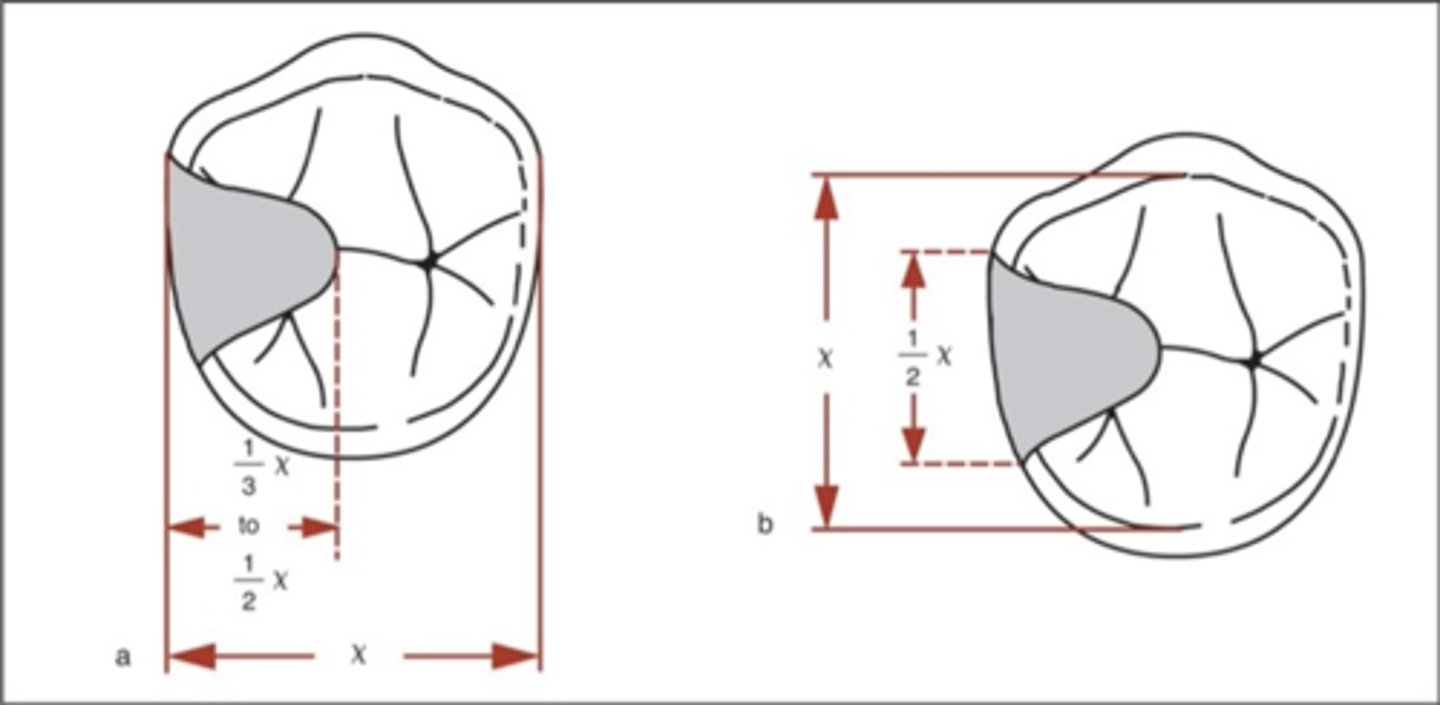

Occlusal rest

note: an extended occlusal rest is helpful when a molar abutment is mesially tipped, to enhance force down the long axis of the tooth (vs a more distally-directed force with a shorter mesial occlusal rest). If <1mm, the rest will break off!

inner

In an occlusal rest, the _______ portion must be located more apically than outer portion near marginal ridge (positivity). May or may not require tooth preparation. If the angle between minor connector and inner portion of rest is ≥90°, occlusal forces will act to slide the rest away from the tooth